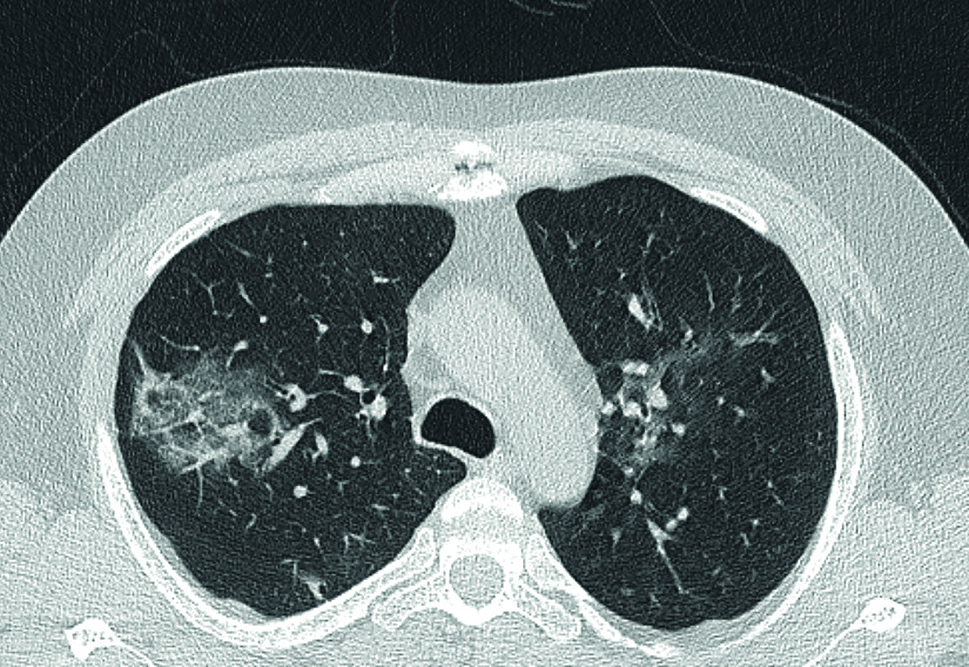

Vzhledem k tomu, že šlo o imunosuprimovaného pacienta po prodělané pneumonii v roce 2019 se závažným průběhem a nyní s manifestovaným trombofilním stavem, doplnili jsme druhý den hospitalizace výpočetní tomografii s vysokým rozlišením (HRCT) plic s nálezem oboustranných cárovitých kondenzací typu mléčného skla v plicním parenchymu (obr. 1). Dle zobrazovacích metod byl kmen plicnice bez dilatace s normálními parametry.

OBR. 1 HRCT – na snímku v koronárním a axiálním řezu nález kondenzací typu mléčného skla s predilekcí v pravé plíci (Bc. Hrdličková, Bc. Zapletal, MUDr. Šmejkal).

HRCT – výpočetní tomografie s vysokým rozlišením.